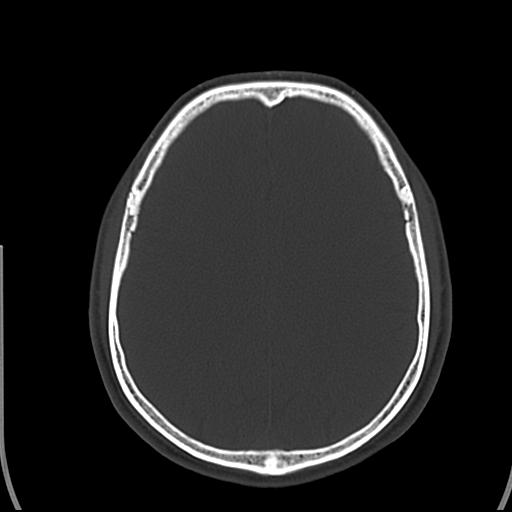

标题: CT25435:头皮下高密度影???

头皮下高密度结节影???临床上在老年男性比较常见。大家看看是什么?成因是? 本例患者,男性,51岁。外伤来诊。无染发史及发根植入史。

皮下钙化点

没见过,可能为毛囊钙化。

考虑钙化。